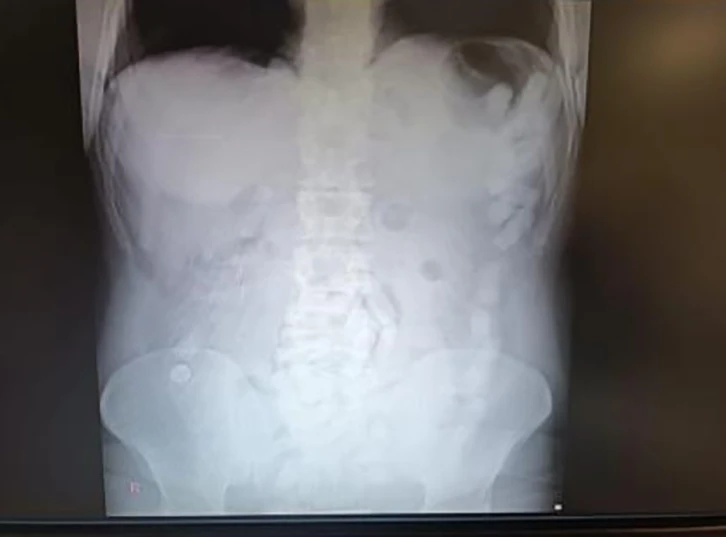

Kayseri’de polis ekipleri tarafından gözaltına alınan şahsın midesinden çıkan 100 kapsülde toplam 729 gram uyuşturucu madde olduğu belirlendi.

Edinilen bilgiye göre, Kayseri İl Emniyet Müdürlüğü Narkotik Suçlarla Mücadele Şube Müdürlüğü ekipleri yabancı uyruklu bir şüphelinin ülkeye giriş yaparak Kayseri’ye geleceğini tespit etti. Şahsı takibe alan ekipler, yerini tespit ettikten sonra operasyon düzenledi. Kayseri Şehir Hastanesinde ultrason çekimi ile yapılan kontrolde şahsın midesinde çok suyada kapsül olduğu tebpit edildi. YApılan operasyonla şahsın midesinden çıkarılan 100 adet kapsülün içerisinde 729 gram uyuşturucu madde ele geçirildi. İşlemlerinin ardından adliyeye sevk edilen şüpheli, çıkarıldığı mahkemece tutuklanarak cezaevine gönderildi.